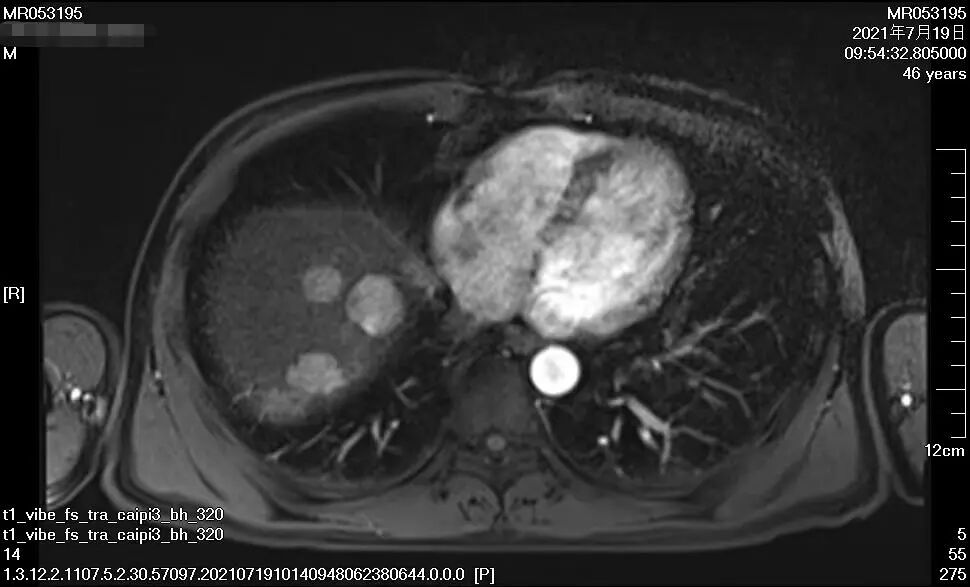

▲上圖1、2為馬先生接受治療兩月后

下圖3、4為馬先生接受治療一年后

經過整整一年的時間,16次靶向+免疫治療,近日,馬先生進行肝臟增強CT復查顯示,腫瘤相比一年前已經小了太多,“對于馬先生這種情況的肝癌患者而言,能取得這樣的療效真的是非常不容易,我們相信在接下來的進一步治療與馬先生自身積極態(tài)度下,一定能‘捷報頻傳’!”腫瘤二科主治醫(yī)師楊長命說。